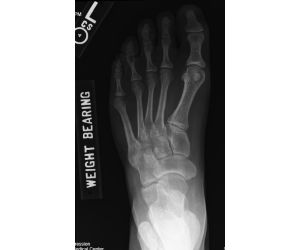

Progressive collapsing foot deformity with tibiotalar arthritis… a challenging problem

Jordan Sisto, DPM, FACFAS

Here we have a 69 y/o male with staged TAA on right that led to AVN talus and collapse which ultimately was revised to TTTA with great success -...